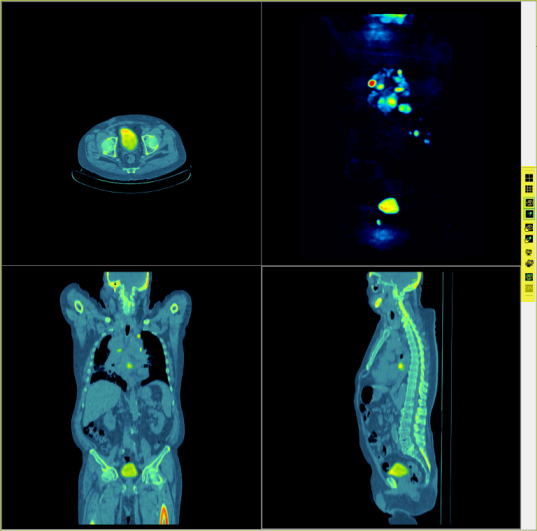

| 4-up | Displays the individual or fused series in all three orthogonal views, plus one MIP view. |

MIP Image View

A MIP view of an individual or the fused image is available in 4-up display mode.